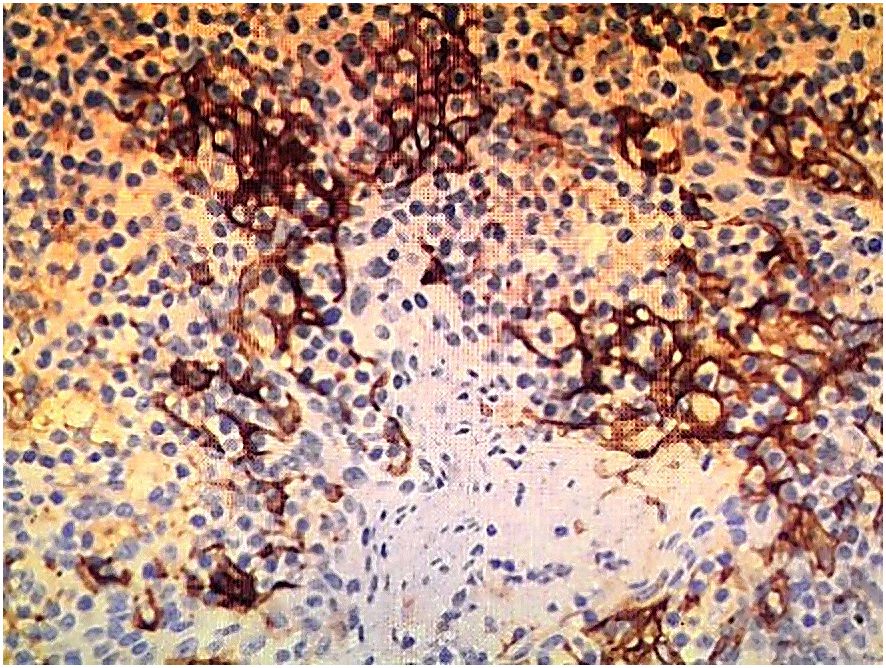

Contrast-enhanced abdominopelvic computed tomography (CT) revealed concentric thickening of the distal left ureter (1.8 × 1.5 cm), with upstream hydroureteronephrosis and an enlarged ipsilateral external iliac lymph node (short axis: 1.2 cm) (Figure 1). ^18F-FDG PET/CT demonstrated intense radiotracer uptake in the ureteral lesion (SUVmax 8.2) and in the lymph node (SUVmax 5.6). Ureteroscopic biopsy revealed sheets of small hyperchromatic cells with nuclear molding and a high mitotic index (>20 mitoses/10 HPF) (Figure 2).

Figure 1

CT scan image showing an axial cross-section of the abdomen, with various organs and structures visible, including the spine in the center and surrounding tissues. The image is in grayscale, highlighting different densities.

Figure 1. Contrast-enhanced abdominopelvic CT demonstrates circumferential thickening of the distal left ureter (1.8×1.5 cm), associated with proximal hydroureter.